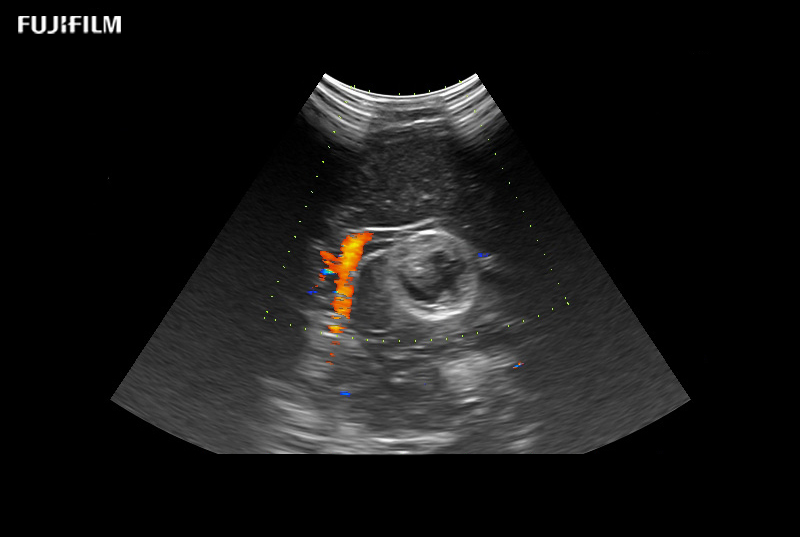

Provides clearer delineation between tissue and blood flow compared to conventional Color Doppler. Even low velocity flow can be imaged with high sensitivity.

Real-time B- and Color Flow modes can be displayed side-by-side, offering an easier anatomical interpretation of blood flow.